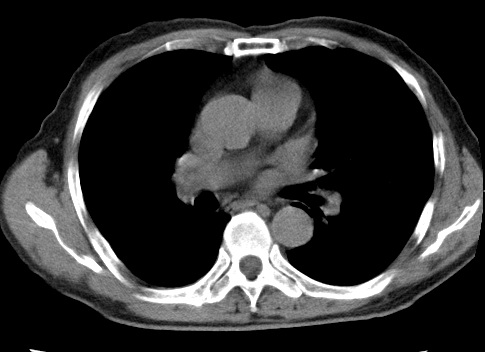

标题: CT23975:女61岁,腹部不适,明显消瘦 [打印本页]

标题: CT23975:女61岁,腹部不适,明显消瘦

既往5年前卵巢癌行子宫及附件切除,右乳癌术后一年,考虑腹膜转移?

大量腹水,考虑腹膜转移。肝脏低密度灶。1囊肿,2转移。

1)结合病史,考虑腹膜及网膜转移瘤。2)肝脏多发性低密度灶,不排除转移瘤。3)大量腹水。

考虑卵巢癌行子宫术后复发,并肝、腹腔 、大网膜转移可能性大。

大量腹水。